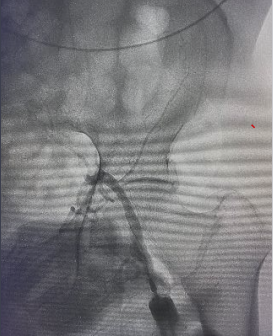

头颈部血管造影提示:患者为右侧颈内动脉极重度狭窄合并右侧大脑中动脉闭塞。

由远及近,优先开通右侧大脑中动脉恢复颅内血流,再行右侧颈内动脉起始部支架植入血管成形,顺利开通闭塞血管,颅内血流恢复。